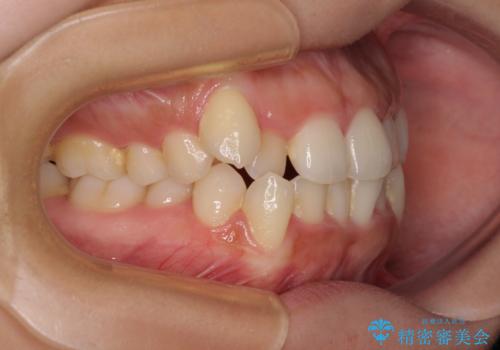

上顎歯列が下顎の歯列に対して狭小であり、一部下顎の奥歯が上顎よりも外側に位置している状態でした。

上顎の急速拡大装置を使用して上顎骨を側方に拡大することで上顎歯列を拡大し、下顎歯列も拡大できるようにすることで、歯列を整えることとしました。